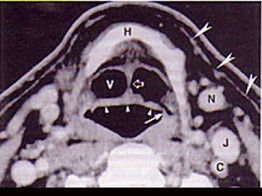

男,55歲,聲嘶6年,有長期吸煙史。檢查:無呼吸困難。喉鏡檢查:聲帶慢性充血,可見右側(cè)聲帶可見菜花樣新生物,右側(cè)聲帶活動(dòng)固定,喉部CT檢查如下圖: